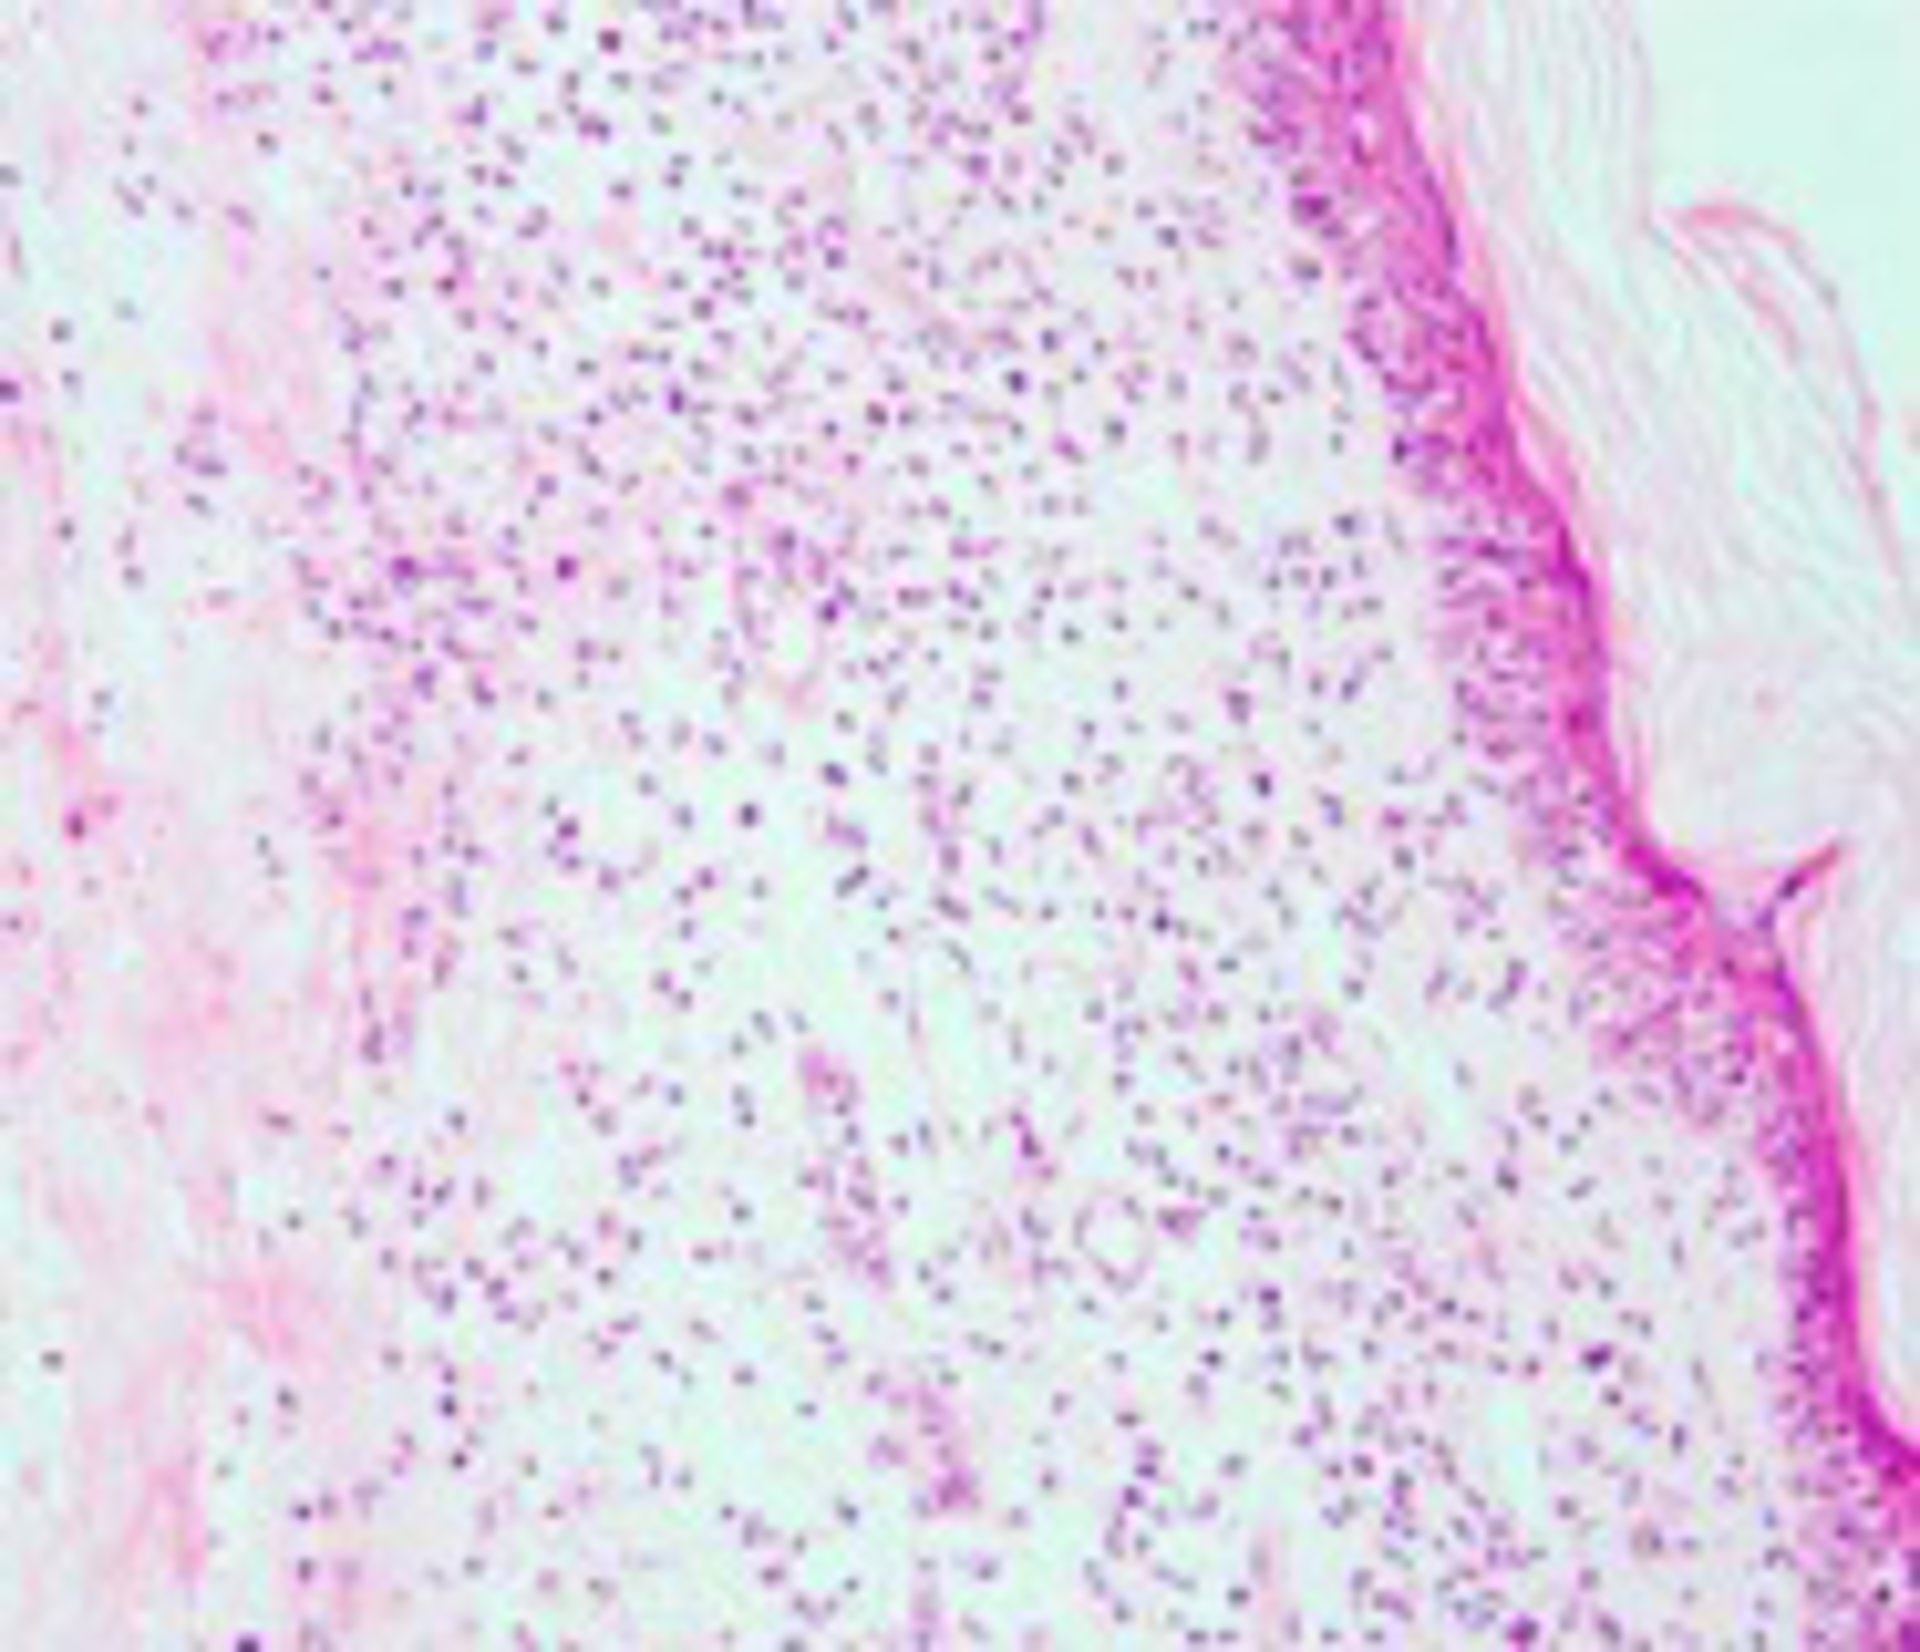

El estudio, que se publica en la revista Nature Communications, se ha realizado en ratones con el modelo de la viruela, una de las enfermedades más virulentas a las que se ha enfrentado el ser humano (causó la muerte de millones de personas antes de su erradicación) y la primera enfermedad infecciosa erradicada mediante un programa global de vacunación en 1980.

El mecanismo combinado contra quimioquinas y el factor de necrosis tumoral, ideado por estos virus, hace que al eliminar la proteína viral pierda la batalla contra el sistema inmune y el virus sea incapaz de causar la enfermedad. De esta forma, el efecto antiinflamatorio de los receptores del TFN se ve potenciado.